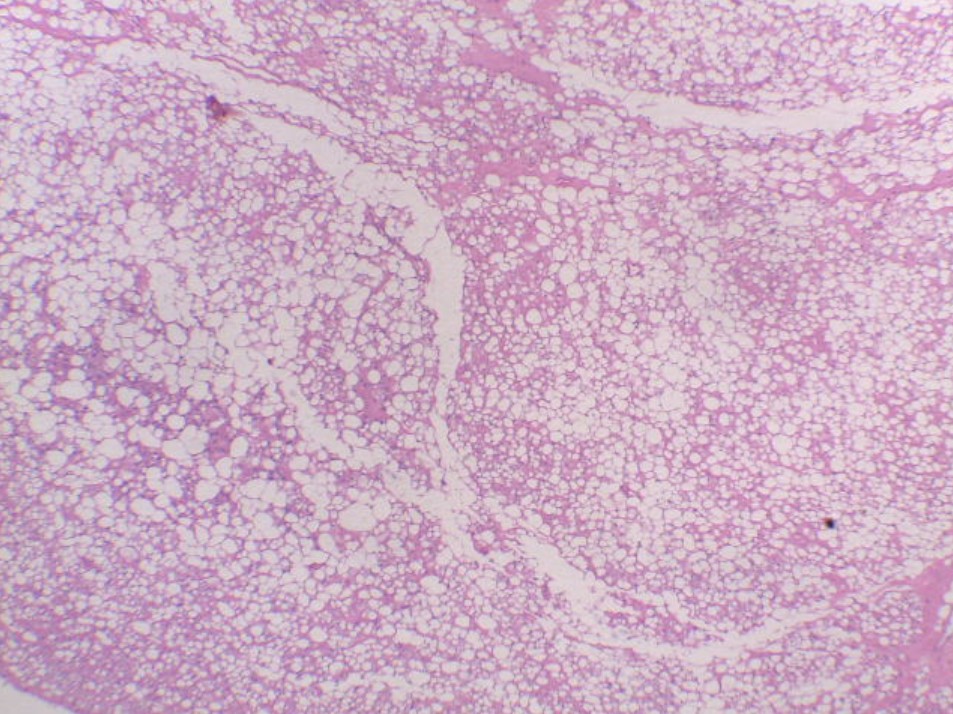

Mujer de 45 años con tumor en muslo derecho de lento crecimiento. Se realizó resección amplia de la lesión.

Lipoma condroide